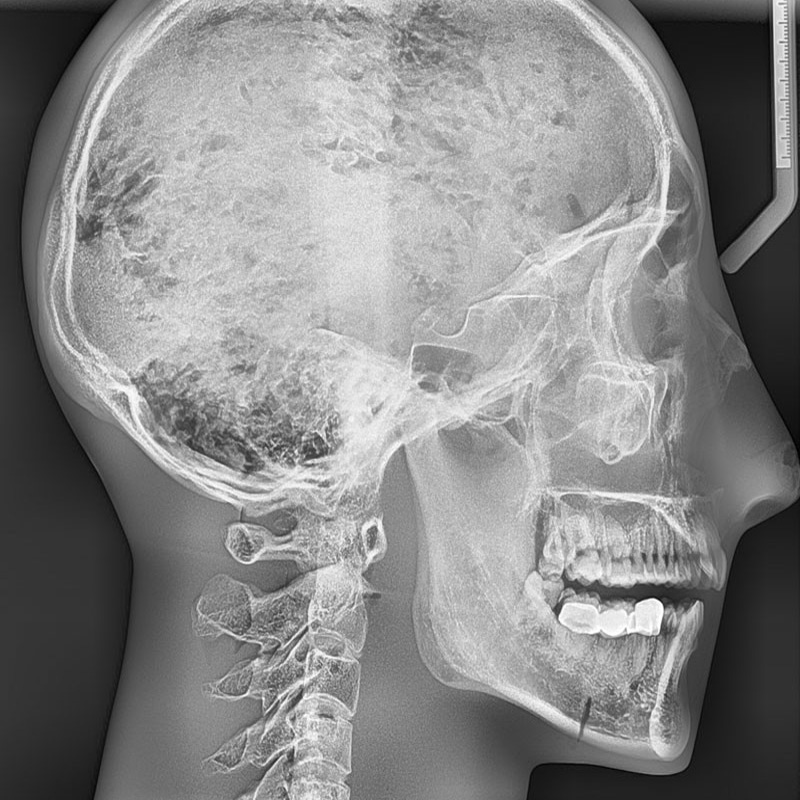

1.模型包含具有天然齿列的真实人类颌骨和5-7截颈椎,整体包埋于软组织等效材料中

2.头骨是医学教学用头骨,没有降解迹象

3.牙齿为未脱落的天然牙齿,部分牙齿有牙科修复痕迹。

4.模式可显示完整的头部骨骼解剖结构,但是没有软组织或软骨解剖,没有气管

人类头盖骨与下颌骨及五节颈椎